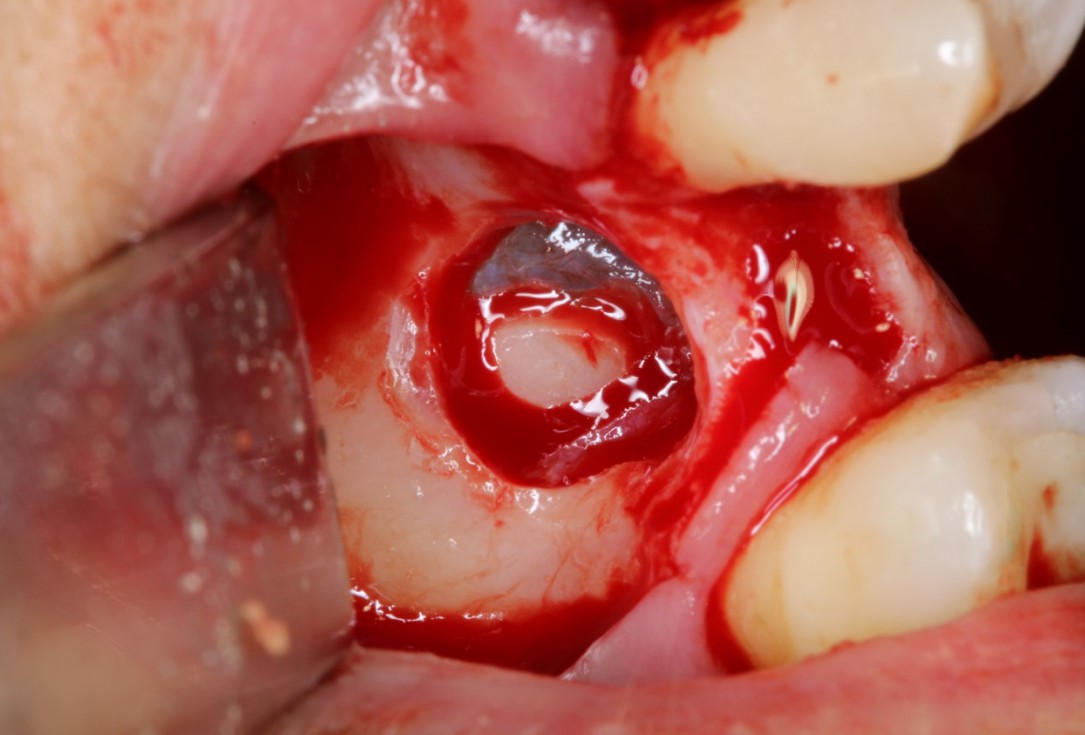

Clinical situation: 71-old patient with atrial fibrillation and Warfarin medication